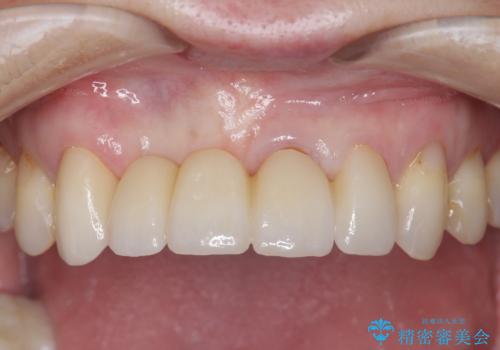

美容外科による不自然なかぶせもので、前歯がコンプレックスに。自然なセラミックにやりかえ 30代女性